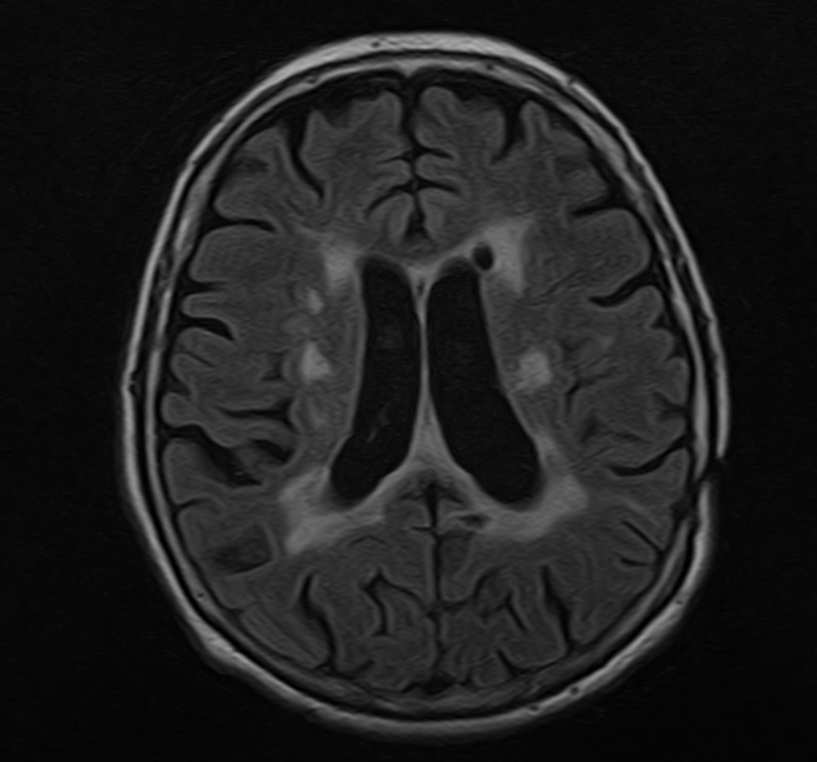

Ниже привожу пример МРТ-изображения головного мозга пациента с последствиями приема левамизола для убедительности. На изображении все «белые пятна» - это патологические изменения.

Одно из самых тяжелых осложнений приема лекарства – энцефалопатия, которая является следствием аутоиvмунного поражения головного мозга. Максимально ее риск проявляется в интервале от 2 до 5 недель после приема левамизола.

Пациент с такой индуцированной приемом Декариса энцефалопатией начинает жаловаться на нарушение памяти, внимания, трудности при подборе слов, эмоциональные нарушения, нарушения сна, могут появиться двигательные симптомы и даже нарушения сознания.

Это может стать тяжелым заболеванием, которое повлечет за собой госпитализацию и не всегда завершается восстановлением даже после правильного и своевременного лечения. Последствия энцефалопатии могут остаться с человеком в виде нарушений памяти, утраты работоспособности, двигательных или других нарушений.